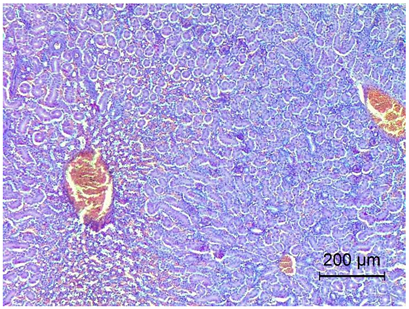

Table 4. Histopathology results of Pekin ducks with short beak and dwarfism syndrome (SBDS).

OrgansSBDS GroupNo. of Figs

Liver Mild interstitial inflammatory infiltrates of heterophilic cells.

Hepatocyte vacuolation.

Congestion.

Applsci 14 08637 i003